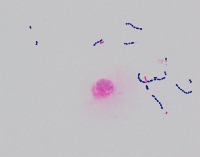

Medical Research: This model can be utilized in the field of medical microbiology and research to classify bacterial strains based on their visual characteristics in lab experiments and for the study of bacterial growth processes.

Healthcare Diagnostics: In healthcare, the "assembly" model could be used to assist in bacterial diagnosis in clinical lab settings, identifying the presence of specific forms of bacteria like Staphylococcus, Streptococcus, B-catarrhalis, Str_pne, and Enterococcus in samples.